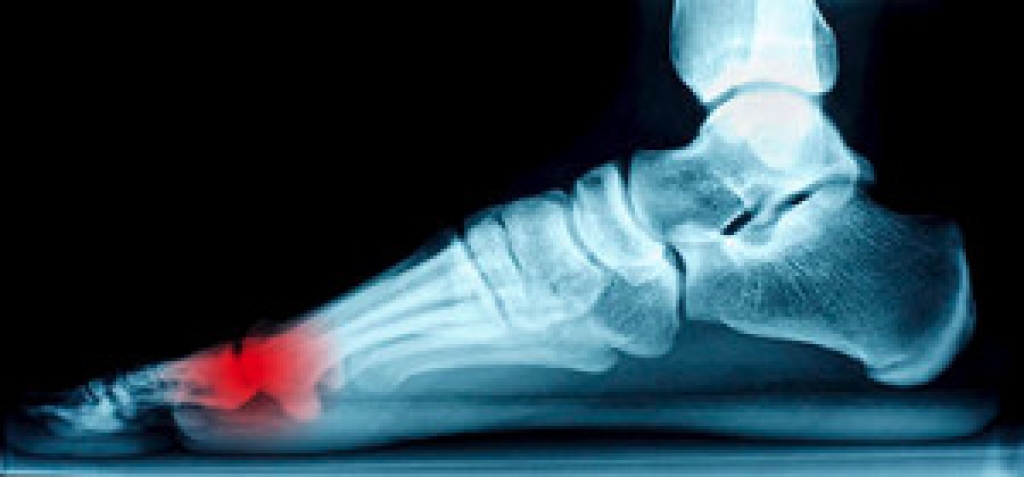

If you experience pain between the ball of the foot and the big toe, you may have a condition referred to as sesamoiditis. It originates from the sesamoid bones, which can be found under the big toe. If the foot has a high arch, these tiny bones endure additional pressure while walking or running. The purpose of the sesamoid bones is to propel the foot forward while walking, which may become difficult to accomplish if they become injured. The symptoms typically consist of pain in the foot while walking, in addition to becoming red and swollen. Wearing a shoe with adequate padding will aid in attaining a certain amount of relief and may take a portion of the pressure off the sesamoid bones. Additional treatment techniques may consist of binding the big toe, which may limit movement, and utilizing crutches to keep the weight off the foot. Please schedule a consultation with a podiatrist if you would like additional information about sesamoiditis.

Sesamoiditis is a condition of the foot that affects the ball of the foot. It is more common in younger people than it is in older people. It can also occur with people who have begun a new exercise program, since their bodies are adjusting to the new physical regimen. Pain may also be caused by the inflammation of tendons surrounding the bones. It is important to seek treatment in its early stages because if you ignore the pain, this condition can lead to more serious problems such as severe irritation and bone fractures.